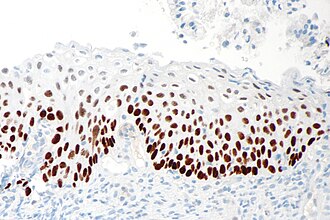

Ki-67

Ki-67 IHC

p16

p16 IHC

p63

p63 IHC

High grade squamous intraepithelial lesion